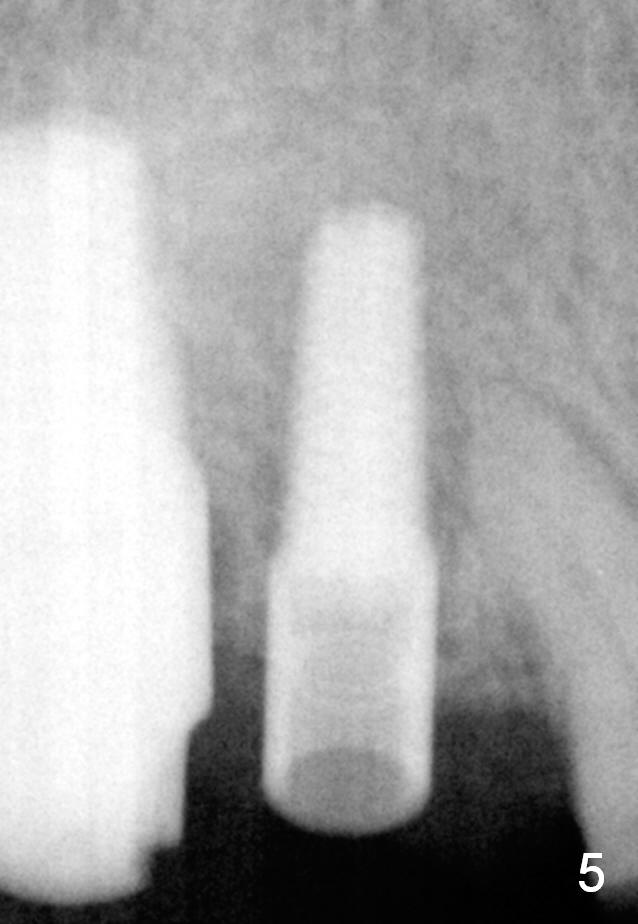

The implant at the site of #3 is intentionally placed distal as part of a plan to distalize the teeth #4-6 (Fig.1). Ortho started, but the patient did not want to pursue it. The most efficient way to terminate it is to dislodge every one of brackets/bands. When it is time for restoration for implants at the sites of #3 and 30, it is a challenge to deal with the space mesial to #3. The patient is planning to leave the country in 20 days. Fortunately he agrees to have an extra implant (Fig.2). It must be small in diameter. The initial osteotomy does not go on smoothly, approaching the apex of the tooth #4 (Fig.3 A). The osteotomy is moved distally and the trajectory is changed. It appears to be overcorrected (Fig.4). After re-adjustment, a 3.5x14 mm implant is placed with insertion torque between 15 and 20 Ncm (Fig.5). An abutment is placed with perio dressing applied around it as well as #3 after suturing. When the wound heals and before the patient leaves the country, the abutment is removed.